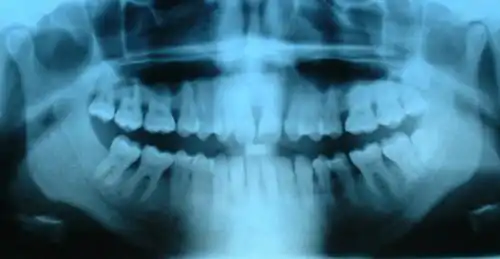

On voit à la fois des dents temporaires et des dents définitives.

Radiographie de dents saines (prémolaires, molaires, dent de sagesse incluse) et cariées (2e prémolaire supérieure et 1re molaire supérieure).